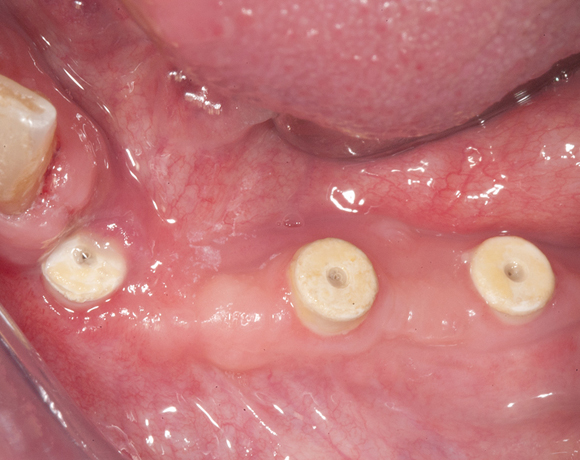

Knochenspaltung Unterkiefer 32 – 36

Die Knochenspaltung auch Bonesplitting genannt, ist eine geeignete Möglichkeit im Unterkieferseitenzahnbereich Knochen aufzubauen, um Implanate setzen zu können. Vorraussetzung ist eine ausreichende Knochenhöhe.

Bei diesem Patientenfall war vor dreizehn Jahren bereits eine Knochenspaltung besprochen

worden, die Patientin hatte allerdings Angst vor dem Eingriff und sich für eine herausnehmbare

Lösung entschieden. Nachdem die endodontisch behandelten Zähne 32 und 33, die mit VMK – Kronen

und Geschiebe versorgt waren, abgebrochen sind, war die Patientin für den Eingriff mit Knochen-

spaltung und drei Implantaten offen. Heute ist sie sehr zufrieden und bereut es nicht gleich diese

Lösung gewählt zu haben.